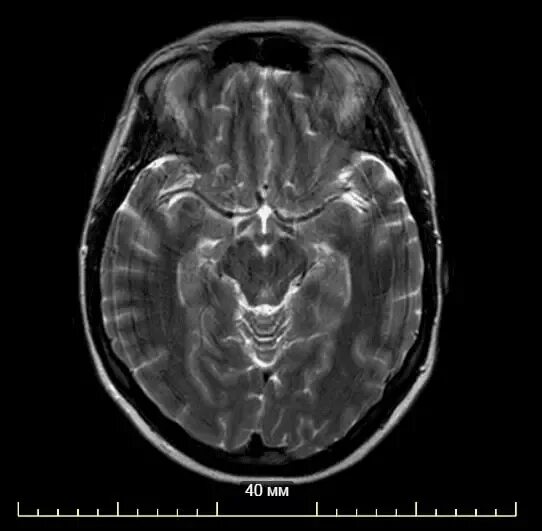

Мрт головного мозга и сосудов тула